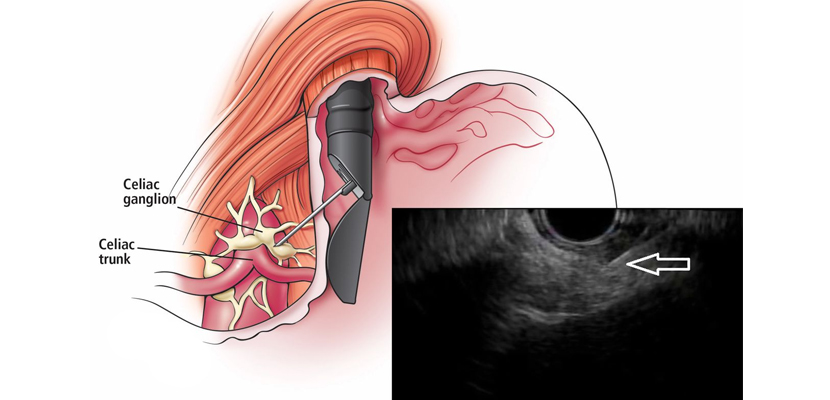

Endoscopic ultrasound-guided tissue acquisition (EUS-TA) is a minimally invasive technique used to obtain tissue samples from deep-seated lesions for diagnostic and therapeutic purposes. It is performed using fine-needle aspiration (FNA) or fine-needle biopsy (FNB), providing a high level of accuracy in evaluating pancreatic, gastrointestinal, mediastinal, and other abdominal lesions.

EUS-TA combines the imaging capabilities of EUS with needle-guided sampling. The procedure involves:

• Localizing the target lesion using high-resolution ultrasound.

• Advancing a fine needle (FNA or FNB) through the endoscope into the lesion.

• Aspiration or coring of tissue for cytological or histological evaluation.